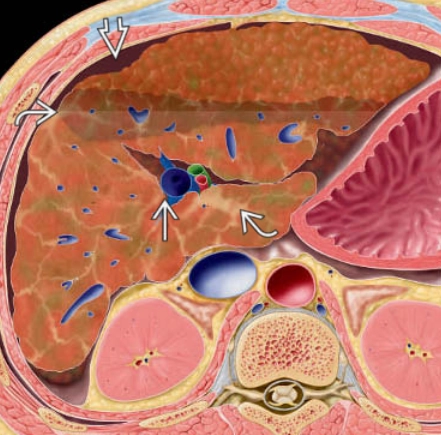

• Gan nhiễm mỡ (Steatotic liver disease)

• Gan nhiễm mỡ khu trú (Focal hepatic steatosis)

• Gan nhiễm mỡ lan tỏa (Diffuse hepatic steatosis)

• Lắng đọng amiodarone trong gan (Amiodarone deposition in the liver)

• Xơ gan (Cirrhosis)

• Gan ứ đọng sắt (Hemochromatosis)

• Gan to (Hepatomegaly)